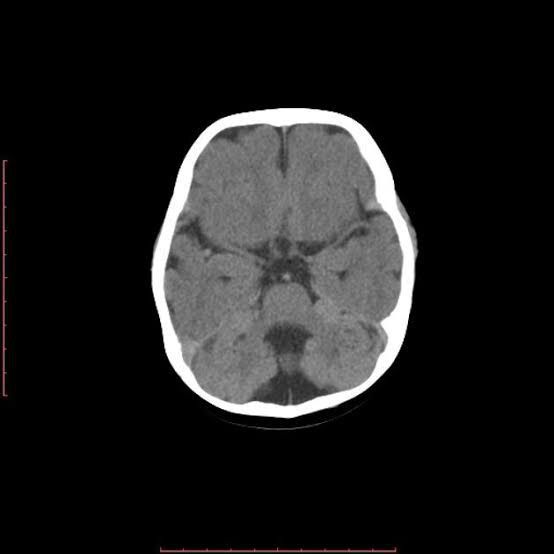

Cerebellar hypoplasia is a neurological condition in which the cerebellum is smaller than usual or not completely developed. Cerebellar hypoplasia is a feature of a number of congenital (present at birth) malformation syndromes, such as Walker-Warburg syndrome (a form of muscular dystrophy.